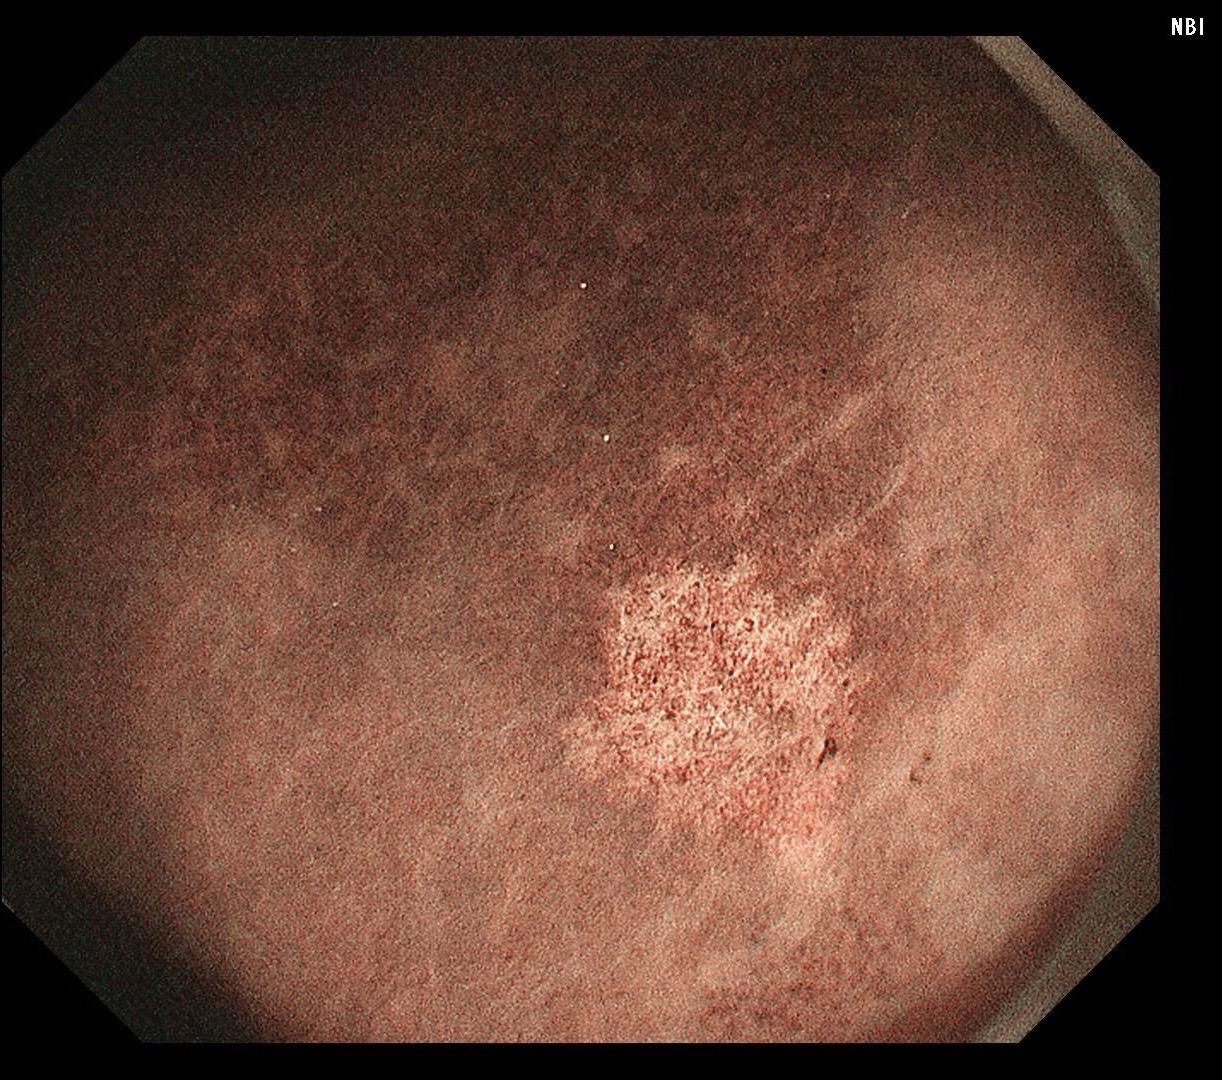

男,40岁,胃双发褪色调病变。慢性胃炎复查,3年前胃镜未见异常,Hp阳性背景,萎缩不明显,胃体下部大弯见一褪色调病变,浅凹陷,5mm左右,换用放大内镜观察,表面结构缺失,血管异型明显,未分化可能性大……胃窦后壁见一白斑,无高度差,NBI浅茶色,放大草草看了下,似有边界,IP增宽,活检待病理……小哥哥胖得几乎没脖子,腹式呼吸太明显~😖